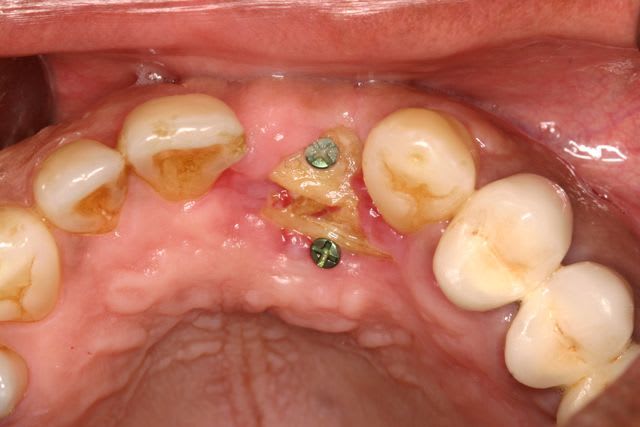

"et 2 beefsteak pour la dame", c'est un peu ce qui c'est passé cet aprem pour cette patiente qui m'a été adressé pour gérer une periimplantite à la mandibule. Et bien sûr, ceux qui ont planté, ne sont en rien préoccupé de l'absence de gencive attachée !! Pourquoi s'embêter, hein ? : t'ouvres, tu plantes et puis tu tractes comme un âne pour pouvoir fermer et puis si tu sutures le versant interne de la lèvre avec le plancher de la bouche ... ca marche pareil ... non?

Et donc mézigue aujourd'hui, avant de pouvoir assainir, a dû recréer un environnement gingival satisfaisant.

Donc pour en revenir à mon cas de cet aprem, en raison d'une absence complète de gencive attachée autour de ces 5 implants mandibulaires, et de par l'absence de vestibule, j'ai réaliser une double greffe gingivale libre de 15mm x 8mm chacune.

c'est de la demie épaisseur. Je n'ai pas de photos du site receveur avant mise en place du greffon dans le cas d cet aprem mais d'un autre cas (le principe est le même) où j'ai en plus pratiqué une implantoplastie :